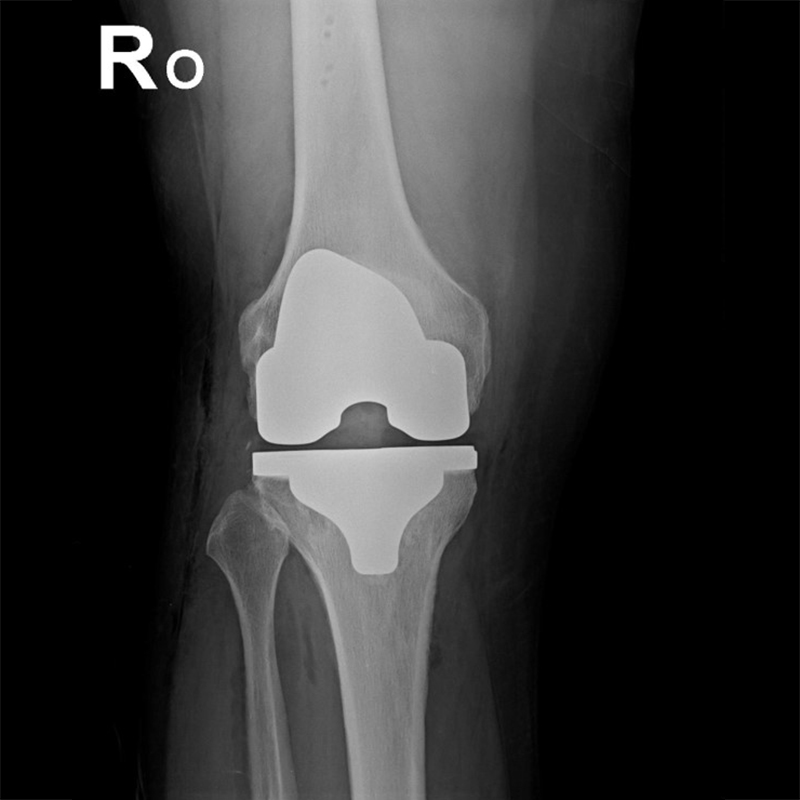

機器手臂手術 首頁 案例分享 膝關節手術 機器手臂手術 蔡女士 78歲 術前 術後 陳女士 70歲 術前 術後 術前 術後 ANGEVINE女士 73歲 術前 術後 U.S.A Mark 73歲 術前 術後 藍女士 78歲 術前 術後